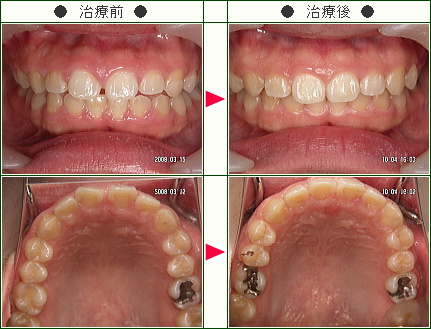

前歯のすきっ歯矯正の治療症例解説(20歳から39歳まで)--部分矯正--その2

☆前歯のすきっ歯矯正症例[Y.H様 24歳 男性]